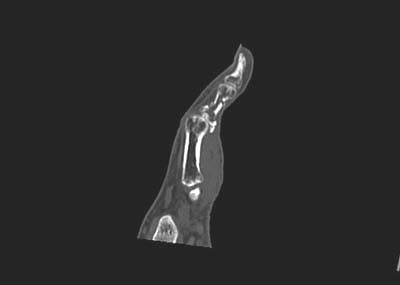

支持以上的诊断:特定的好发部位,没有骨质结构的破坏,骨皮质完整,可以和肿瘤相鉴别。建议必要时行ct扫描可能发现隐秘的骨折线。

请见指骨骨折ct矢状面重建图象观察骨折细节:

[本贴已被 牟言科 于 2006-8-24 17:17:37 修改过]